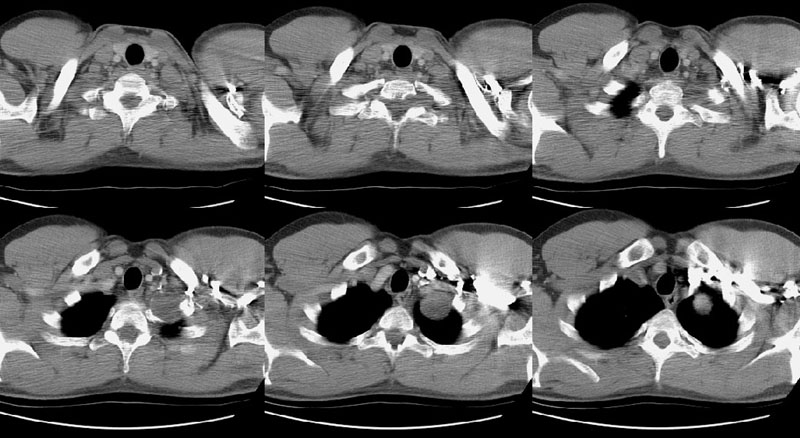

The case below is of a 9 year old girl that presented with an abnormal CXR. A large anterior mediastinal mass is demonstrated on the CT with macroscopic foci of fat attenuation. (Click image to enlarge)